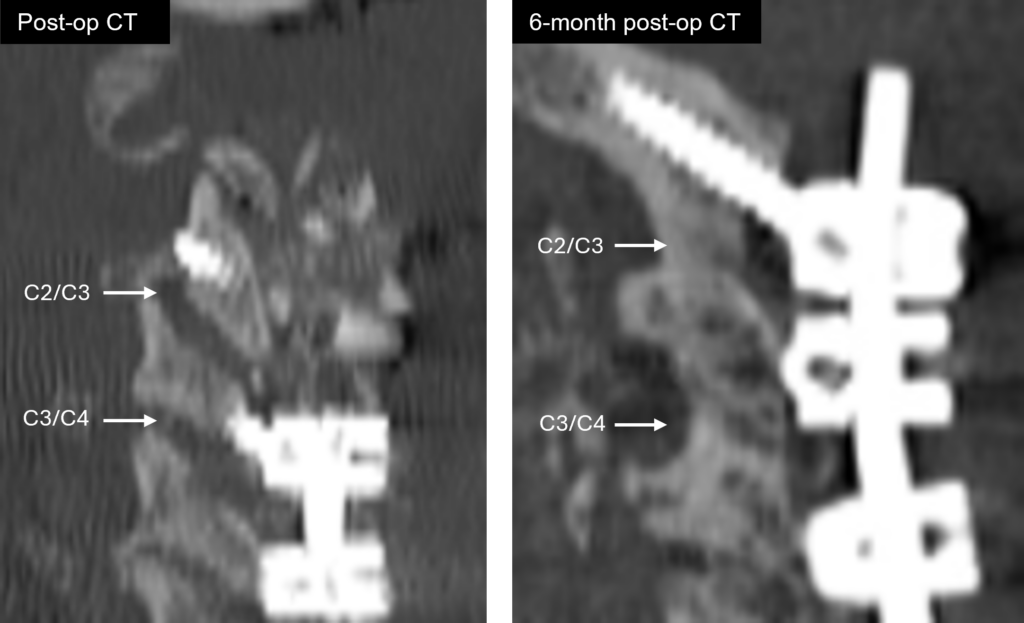

Fuse

NorthStar Facet Fusion

Robust fusion through the facet joint on

6-month post-op CT

Standard of Care

Standard facet burring and eggshell-like fusion over the facet joint